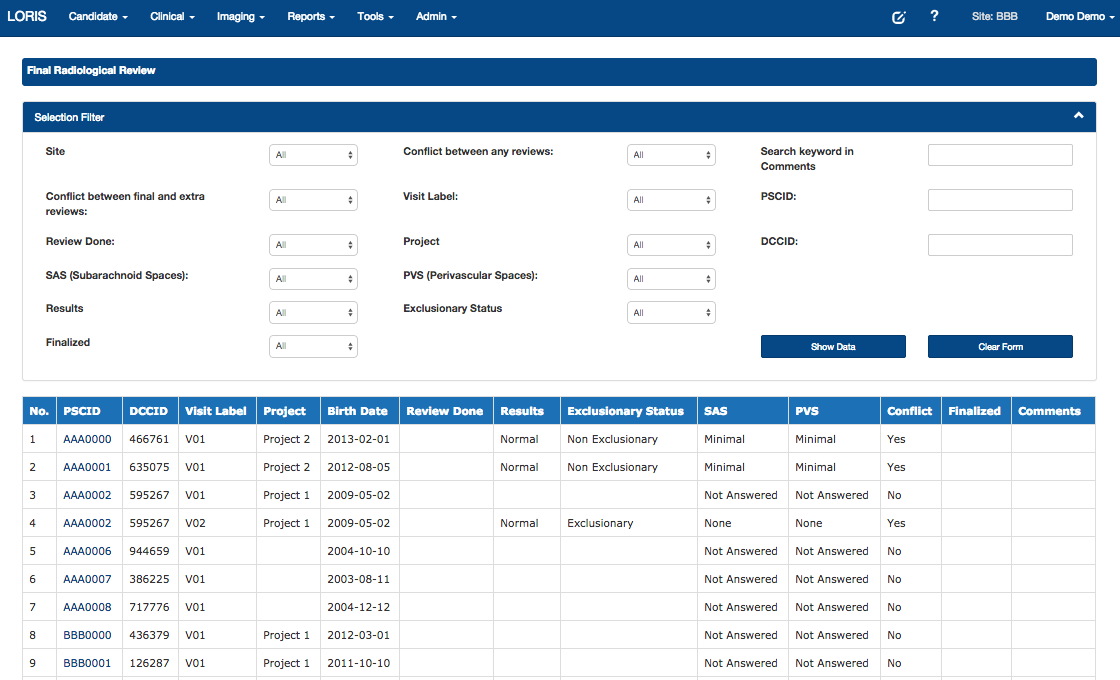

Radiological Review Module, DCC MRIData Querying

- Radiological Reviews - Visualization, including module to curate